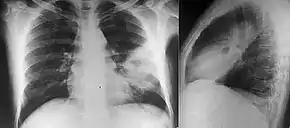

People with diabetes mellitus or regular exposure to the bacteria are at increased risk of developing melioidosis. The disease should be considered in those staying in endemic areas who develop fever, pneumonia, or abscesses in their liver, spleen, prostate, or parotid glands.[1] The clinical manifestation of the disease can range from simple skin changes to severe organ problems.[1] Skin changes can be nonspecific abscesses or ulcerations.[7] In northern Australia, 60% of the infected children presented with only skin lesions, while 20% presented with pneumonia.[3] The commonest organs affected are liver, spleen, lungs, prostate, and kidneys. Among the most common clinical signs are presence of bacteria in blood (in 40 to 60% of cases), pneumonia (50%), and septic shock (20%).[1] People with only pneumonia may have a prominent cough with sputum and shortness of breath. However, those with septic shock together with pneumonia may have minimal coughing.[2] Results of a chest X-ray can range from diffuse nodular infiltrates in those with septic shock to progressive solidification of the lungs in the upper lobes for those with pneumonia only. Excess fluid in the pleural cavity and gathering of pus within a cavity are more common for melioidosis affecting lower lobes of the lungs.[2] In 10% of cases, people develop secondary pneumonia caused by other bacteria after the primary infection.[3]

Various imaging modalities can also help with the diagnosis of melioidosis. In acute melioidosis with the spreading of the bacteria through the bloodstream, the chest X-ray shows multifocal nodular lesions. It may also show merging nodules or cavitations. For those with acute melioidosis without the spread to the bloodstream, chest X-ray shows upper-lobe consolidation or cavitations. In chronic melioidosis, the slow progression of upper-lobe consolidation of the lungs resembles tuberculosis. For abscesses located in other parts of the body apart from the lungs, especially in the liver and spleen, CT scan has higher sensitivity when compared with an ultrasound scan. In liver and splenic abscesses, an ultrasound scan shows "target-like" lesions, while CT scan shows "honeycomb sign" in liver abscesses. For melioidosis involving the brain, MRI has higher sensitivity than a CT scan in diagnosing the lesion. MRI shows ring-enhancing lesions for brain melioidosis.[8]